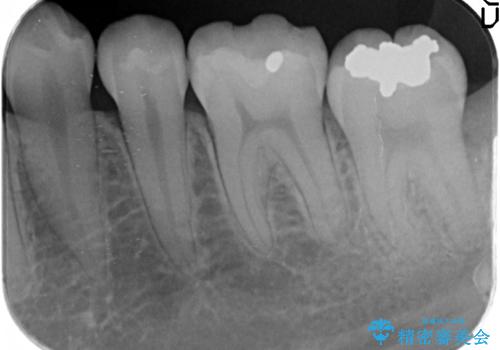

- 古い銀歯を白くしたいといらっしゃった方の症例です。

銀歯及び虫歯を除去後、セラミックインレーにて修復を行いました。

虫歯治療は虫歯の進行度によって処置が変わってきます。

虫歯が小さければ、インレー・クラウン等による修復・補綴処置を行うだけで済みます。

しかし虫歯が大きくなると神経処置や抜歯等をしなければならない場合もあります。

ですので虫歯治療においては早期発見・早期治療が肝要です。